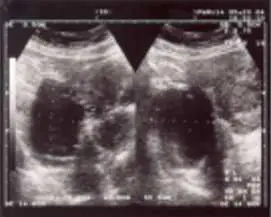

32 歲女性,主訴近年來經痛越來越嚴重,並有性交疼痛及非經期的腹痛。超音波的檢查如圖所示。下列何者對於確認診斷最有幫助?

影像分析:

超音波圖像顯示雙側卵巢均可見圓形囊腫,內部充滿均勻低回音(homogeneous low-level echoes),邊界清楚但囊壁稍厚。此種「毛玻璃樣」均勻低回音為卵巢子宮內膜異位囊腫(endometrioma,俗稱巧克力囊腫 chocolate cyst)的典型超音波表現,係囊腫內含陳舊性血液(液化血塊)所致。雙側病灶合併患者的三大典型症狀(進行性經痛、性交疼痛、非經期骨盆痛),高度懷疑子宮內膜異位症合併雙側卵巢子宮內膜異位囊腫。